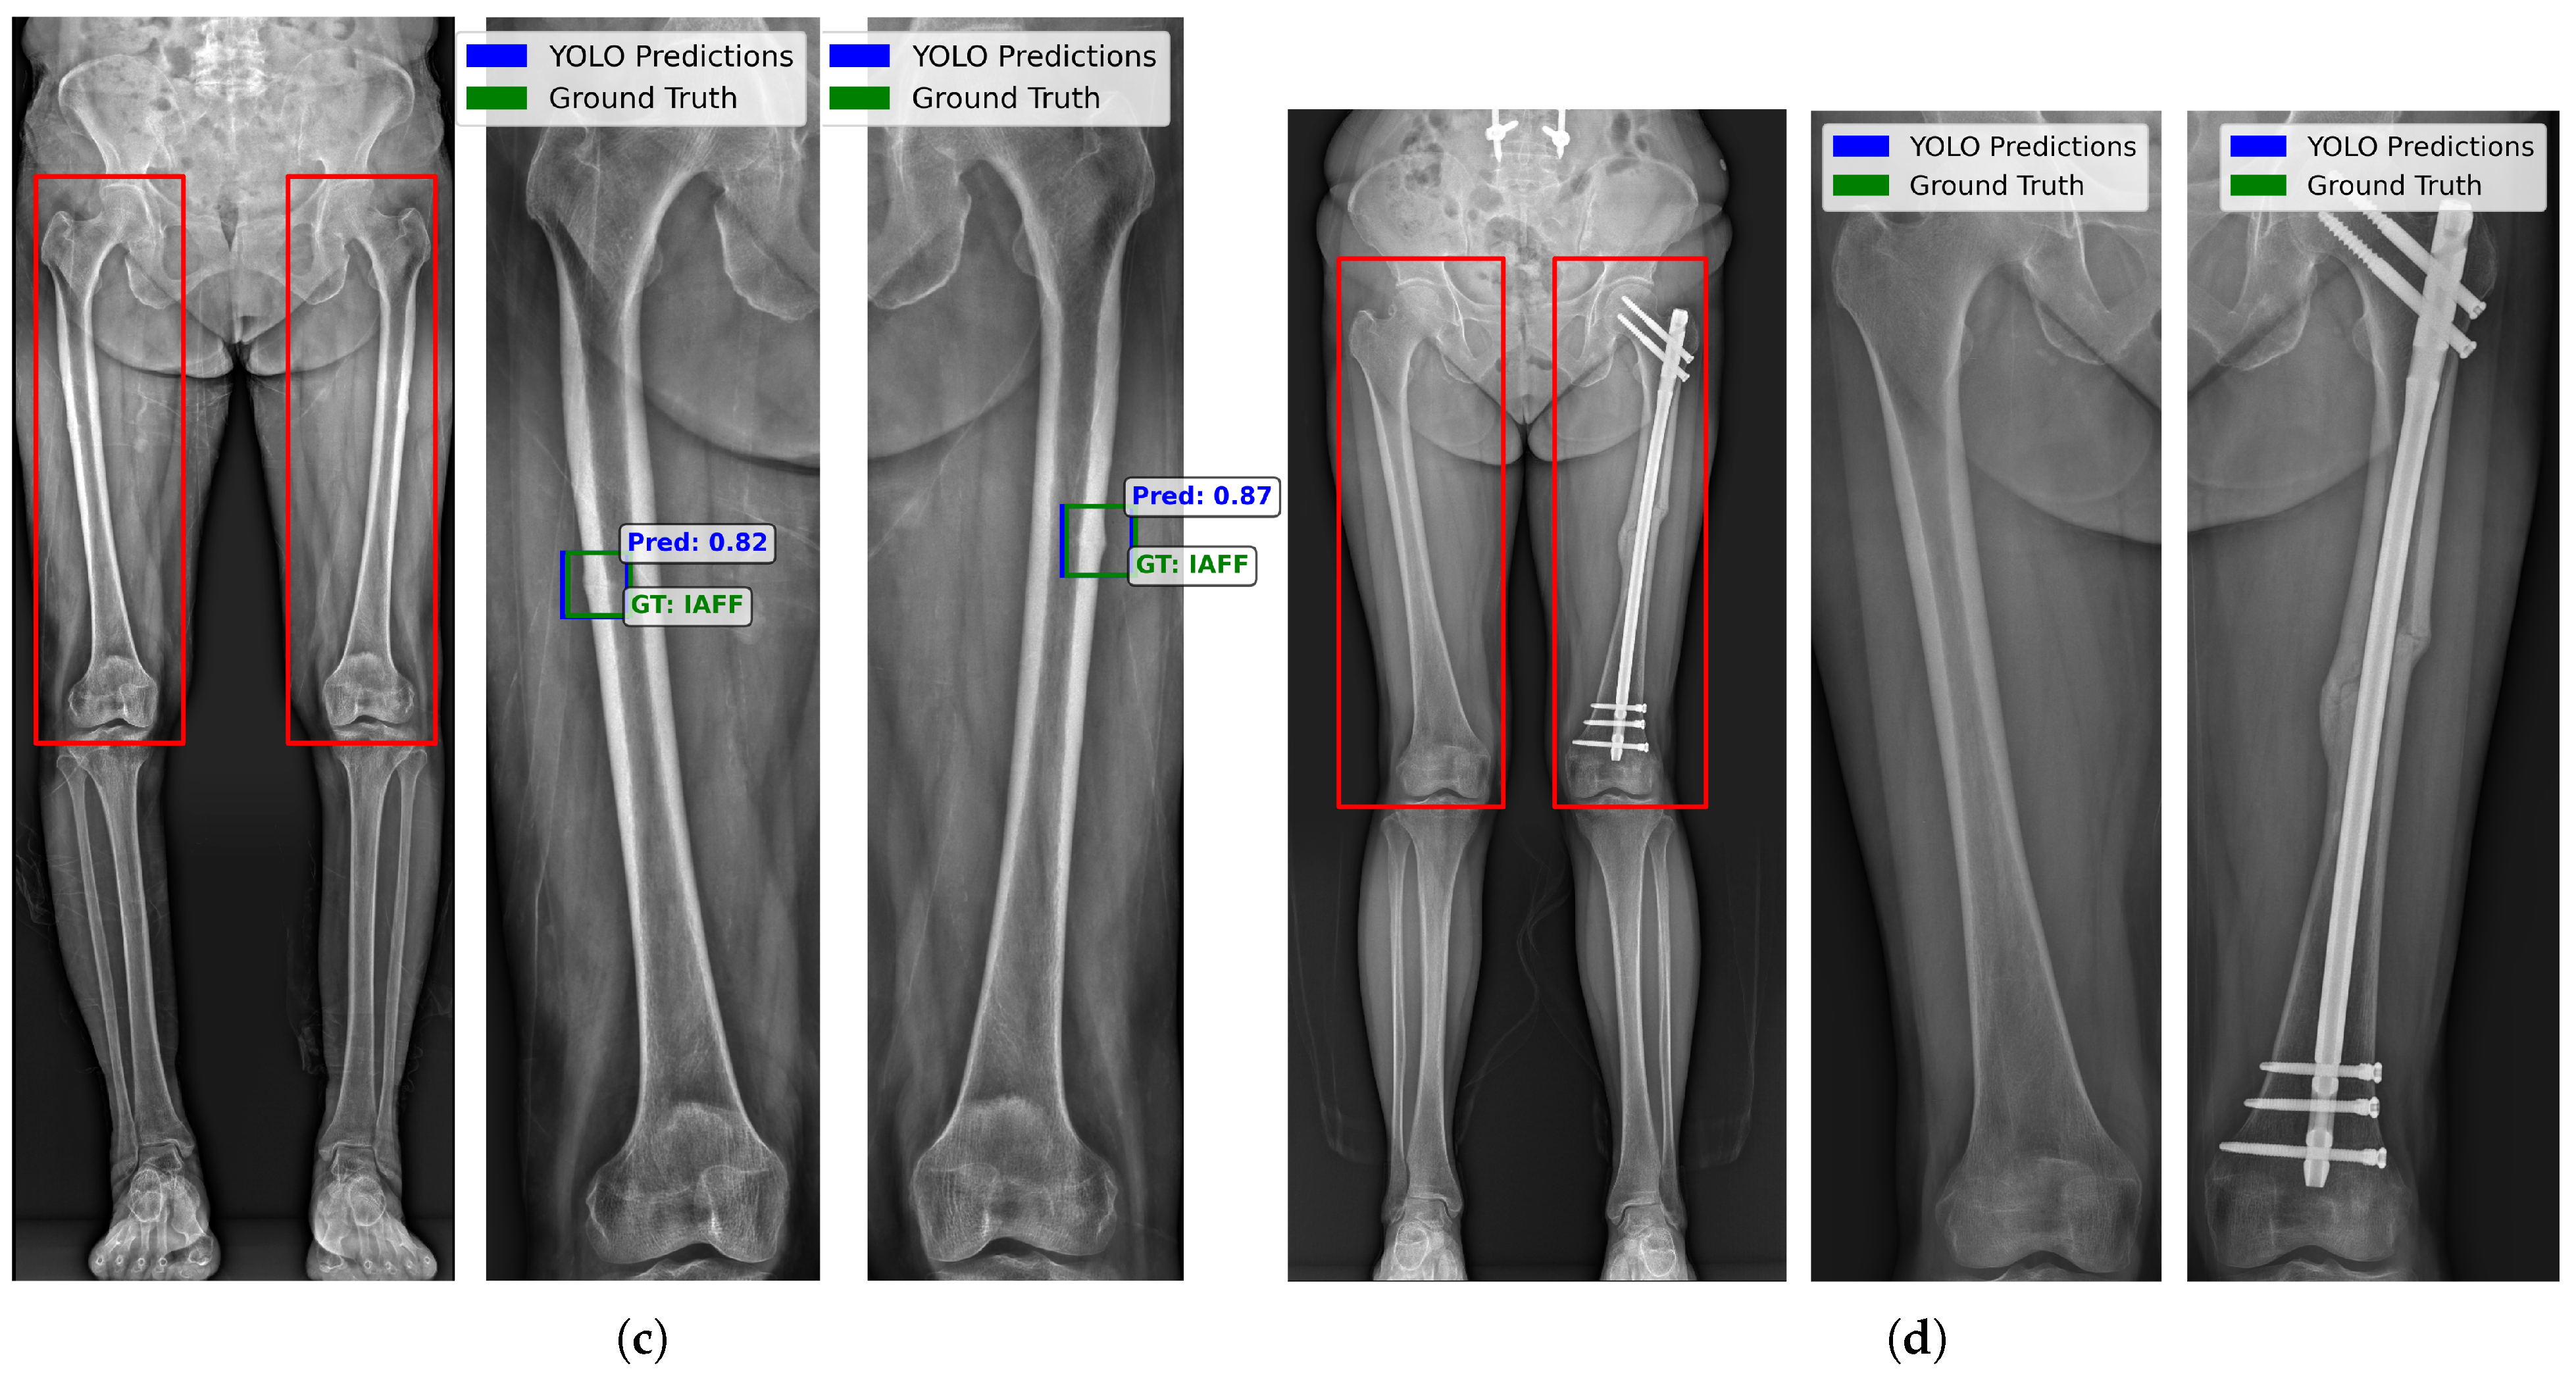

5.4. Visualization of Femoral and Alignment X-Ray

5.6. Zero-Shot Evaluation of Standing AP X-Ray